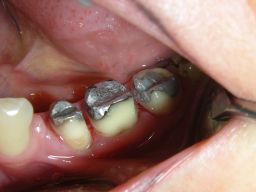

![]() | ||||||||||||||||||||||||||||||||||||||||||||||||||||||||||||||||||||||||

| Gleicher Zahn (37). Zuverlässige Therapie einer schmerzhaften Infraktur, d. h. eines unvollständigen Zahnbruches, mit Amalgam, die mit Composite vermutlich nicht funktioniert hätte. |